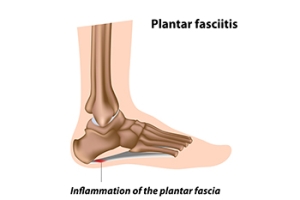

Plantar fasciitis is caused by inflammation of the plantar fascia, a thick band of tissue connecting the heel to the toes. Risk factors include obesity, prolonged standing, high impact activities, flat feet, high arches, and tight calf muscles. Symptoms often involve sharp heel pain, especially with the first steps in the morning or after periods of rest, as well as swelling and stiffness. Causes include overuse, poor footwear, sudden increases in activity, or biomechanical imbalances. A podiatrist can diagnose the condition, recommend supportive footwear or orthotics, provide stretching exercises, and offer treatments to reduce inflammation and restore mobility. If you have heel pain, it is strongly suggested that you promptly contact a podiatrist who can accurately diagnose and treat what may be going on.

What Is Plantar Fasciitis?

Plantar fasciitis is the inflammation of the thick band of tissue that runs along the bottom of your foot, known as the plantar fascia, and causes mild to severe heel pain.

The plantar fascia is a connective tissue in the heel that stretches across the bottom length of your foot. Plantar fasciitis occurs when the connective tissue becomes inflamed, causing heel pain and discomfort during physical activity. Although the condition is completely treatable, traditional methods can take up to a year to start becoming effective.